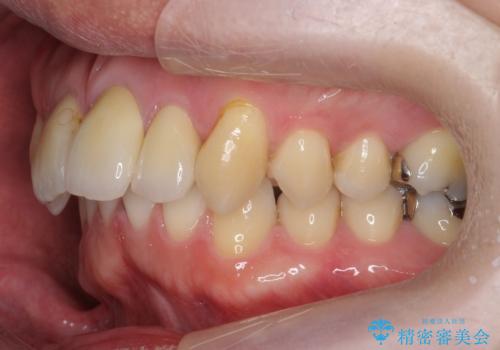

出っ歯を部分矯正で目立たなくする セラミック治療も

- 前歯の突出を主訴に来院。

全体矯正を行うとなると健康な歯を4本抜歯することになるため、歯は抜かず上だけの部分矯正で最小限で前歯を整えることにしました。

前歯は少し細く削って前に出ないように整えました。

左上の1番目の前歯は神経を取ってある歯でした。今後変色もすすんでいくため、治療のやり直しを行いセラミックでかぶせました。

左上の2番目の前歯は虫歯治療を行い、神経治療まで行っています。